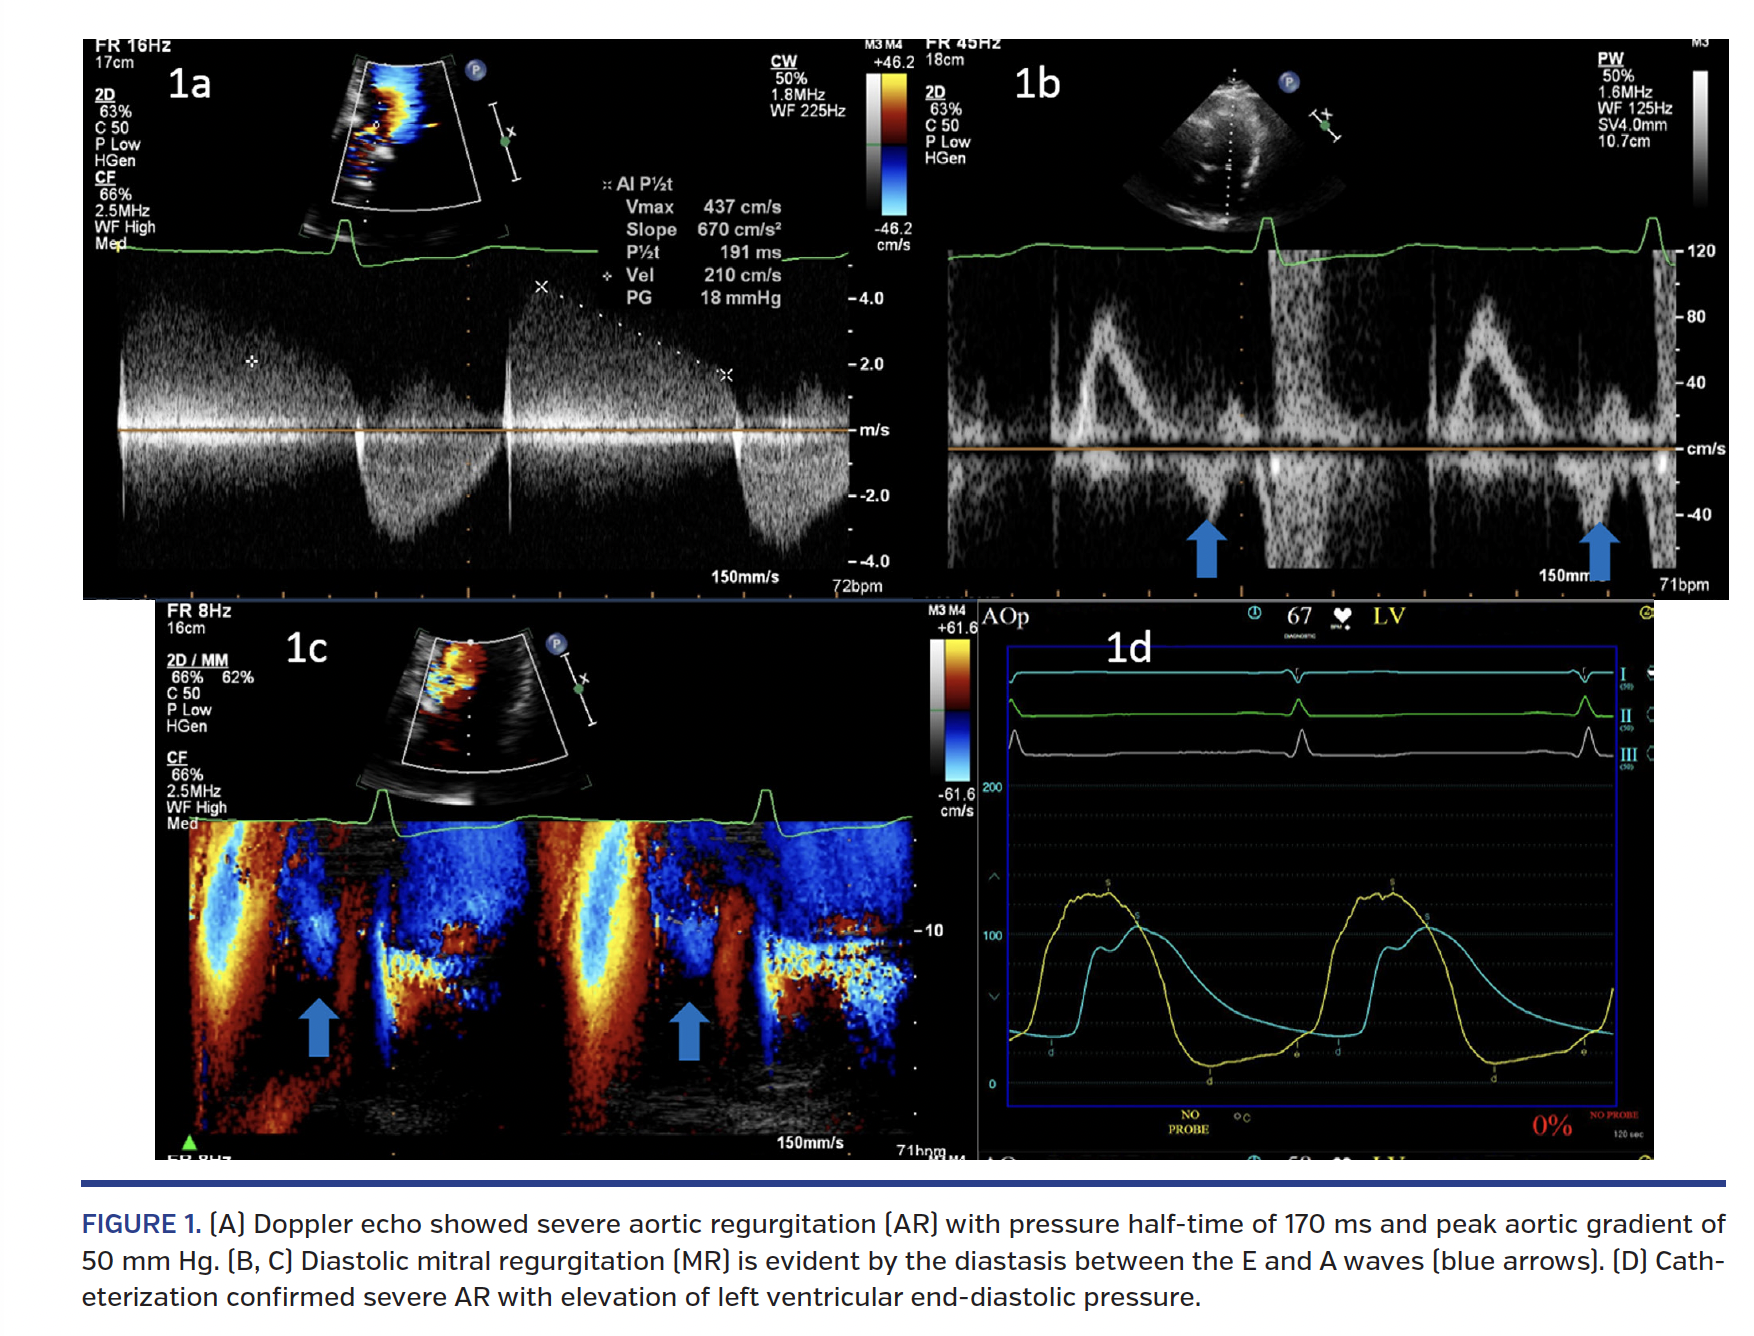

A 57-year-old gentleman was evaluated for symptomatic aortic bioprosthetic valve dysfunction 10 years after aortic valve replacement for aortic stenosis. Doppler echocardiography (Figure 1A) showed severe aortic regurgitation with pressure half-time of 170 ms and peak aortic gradient of 50 mm Hg. Mitral pulsed Doppler and color M-mode Doppler showed diastolic mitral regurgitation in the diastasis between the E and A waves (Figures 1B and 1C, blue arrows). Cardiac catheterization confirmed severe aortic regurgitation with elevation of left ventricular end-diastolic pressure (Figure 1D). Transcatheter aortic valve implantation (TAVI) with a 23 mm CoreValve Evolut R self-expanding valve (Medtronic) reduced the peak aortic gradient to 20 mm Hg with trivial aortic regurgitation (Figure 1E). Post-TAVI Doppler evaluation showed disappearance of diastolic mitral regurgitation (Figures 1F and 1G). Hemodynamic pressure tracings showed normalization of wide pulse pressure and decline in left ventricular end-diastolic pressure from 30 mm Hg to 10 mm Hg (Figure 1H).

Transient elevation of left ventricular diastolic pressure above left atrial pressure can occur in severe aortic regurgitation in the diastasis phase, reflected as the flow reversal at the end of the mitral propagation E wave. This also may be associated with a relatively abrupt deceleration of the E wave as the diastolic mitral regurgitation may eschew part of mid-diastolic inflow to the left ventricle. Post thoracotomy pericardial restraint and persistent left ventricular hypertrophy could also have contributed to the elevation of left ventricular end-diastolic pressure in this patient besides severe aortic regurgitation. The recognition of mitral E wave reversal in such a situation could serve as non-invasive evidence of elevated left ventricular diastolic pressures, thereby guiding therapeutic decision making.